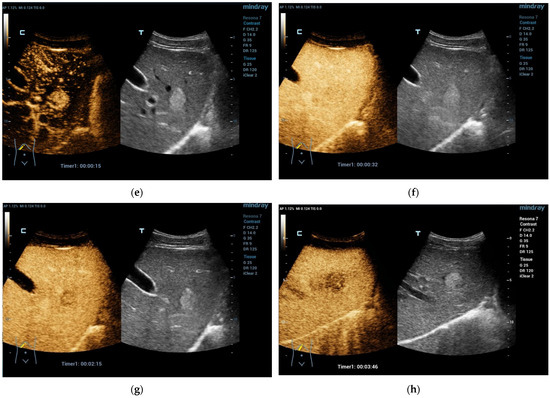

CEUS: CEUS characteristic of pediatric HEHE can refer to the experience of adult groups. During the arterial phase of CEUS, HEHE may show peripheral rim-like or heterogeneous hyperenhancement. In the portal venous phase and late phase, HEHE shows quick washout and becomes hypoenhanced with unenhanced central areas [66,67]. Typical CEUS imaging features reliably allow for effective differentiation between HEHE and other benign FLLs such as hepatic hemangioma and FNH, both showing hyperenhancement and remaining iso- or hyperenhanced in the portal venous and late phase [63] (Figure 3).

Figure 3.

Hemangioendothelioma in a 1-month-old infant. A cystic mass with a maximum diameter of 4 cm in liver segment IV with blurred borders and calcifications with dorsal acoustic shadow (a–e). Evidence of increased vascularization on color Doppler (f). Feeder artery with inflow from the hepatic artery and venous outflow via the markedly dilated left hepatic vein (g). Increased flow velocities in the coeliac trunk and hepatic artery (h,i). Outflowing left hepatic vein with arterialized flow profile and increased flow velocities (j).